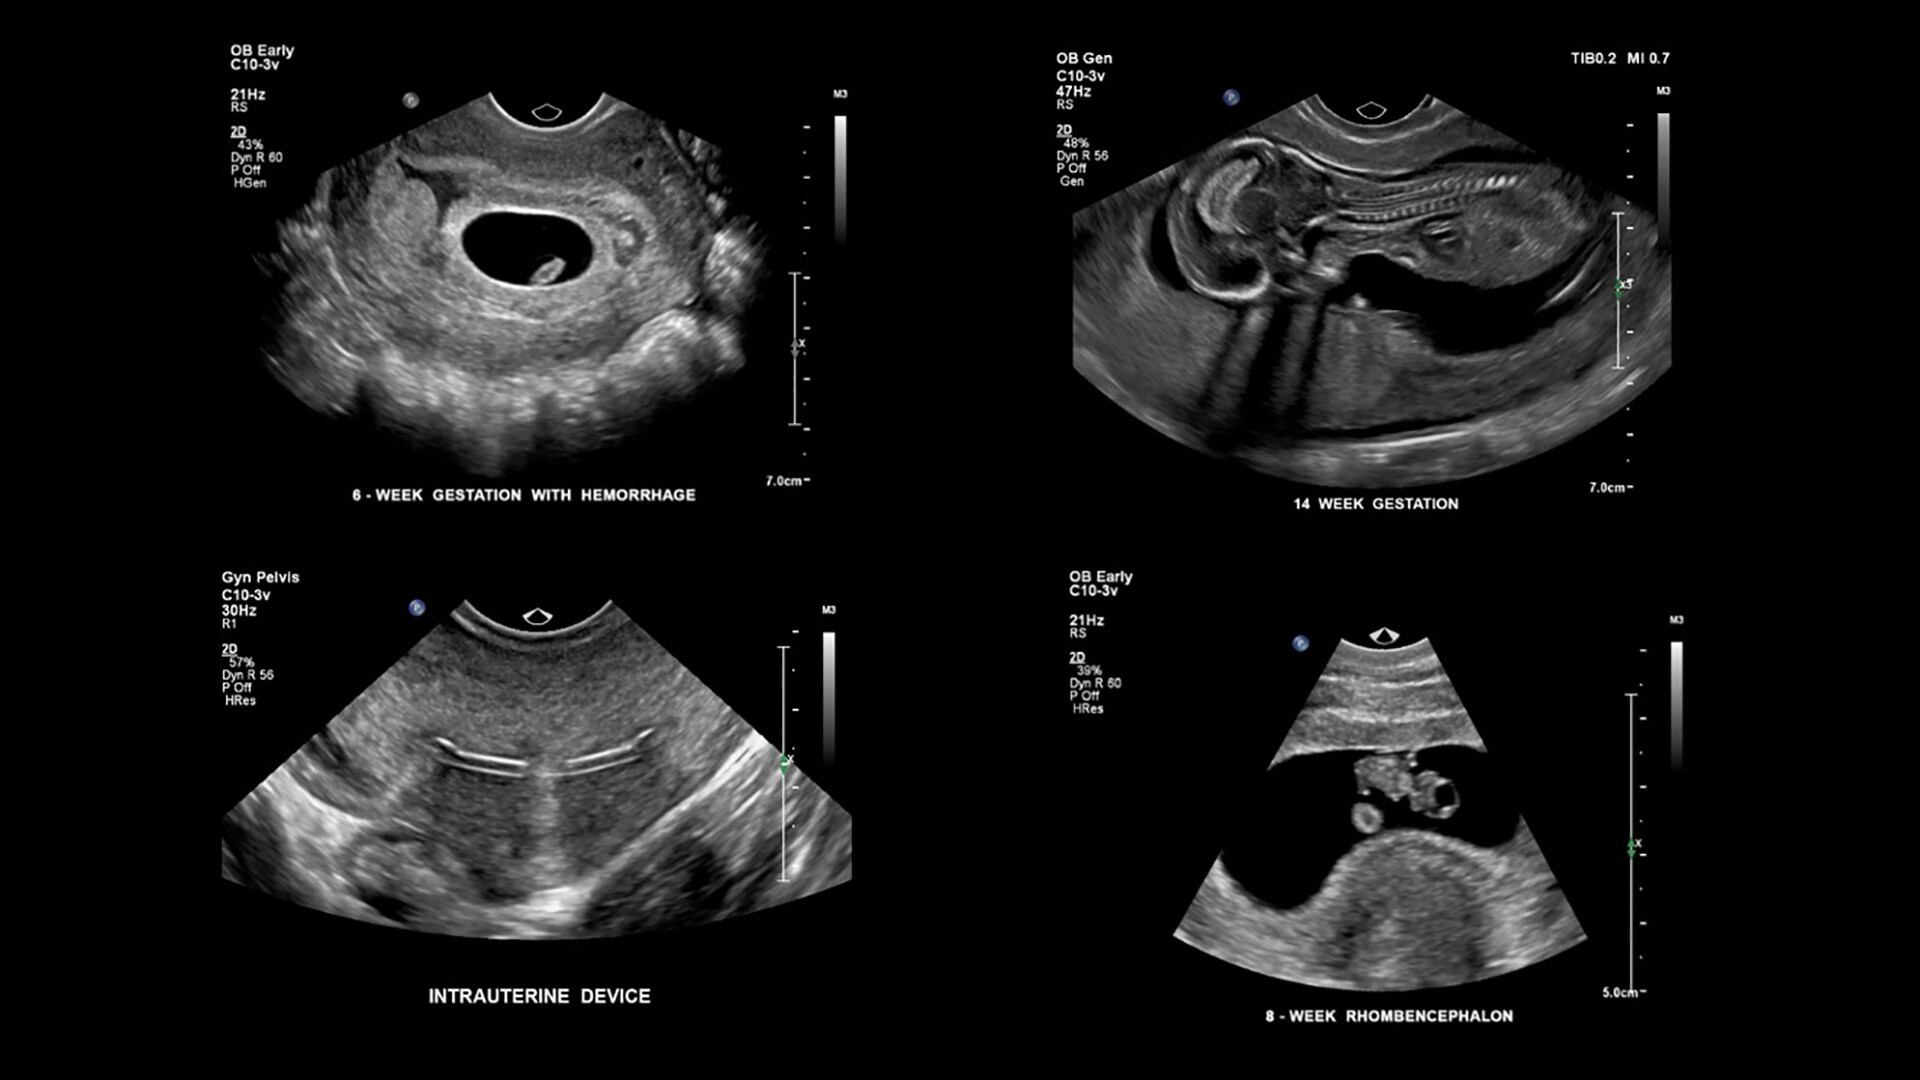

Traductor microconvex C10-3v